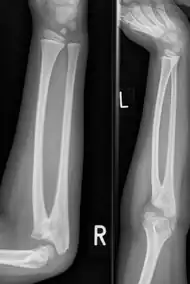

| Congenital radioulnar synostosis in a 7 year old boy | |

It typically causes restricted movement of the forearm, in particular rotation (pronation and supination), though is not usually painful unless it causes subluxation of the radial head.[1] It can be associated with dislocation of the radial head which leads to limited elbow extension.[2]

Diagnosis at birthday is best done using ultrasound technology. In younger children and adults diagnosis is done with x-ray machine at the radioulnar bones.